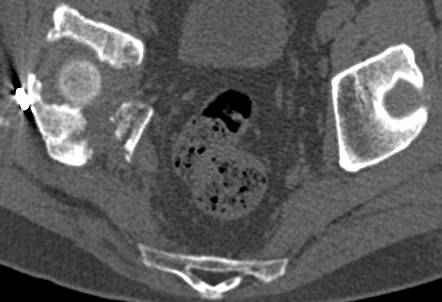

Интересно было бы посмотреть рентгенограммы до операции. У меня впечатление, что я не все вижу, что тут есть... Уважаемые Господа "тазисты" и "тазологи", к какому типу переломов вертлужной впадины по Летурнелю вы бы отнесли это случай?

Из переломов проходящих через крыло и/или заднюю стенку ни простой перелом "передней колонны" (явно имеется пером задней стенки, и не видно перелома седалищной или лонной), ни простой "поперечный", ни ассоциированный "Т-образный" (т.к есть перелом крыла и не видно перелома седалишной), ни ассоциированный "задняя колонна+задняя стенка", на ассоциированный "поперечный+задняя стенка", ни ассоциированный "передняя колонна+задняя гемисфера" (не видно перелома седалищной), ни ассоциированный "обе колонны" (не видно перелома лонной седалищной) не подходят под эту классификацию....

к таковым себя не причисляю, но...обычное дело для нашей страны - выкладывать 3D и не показывать стандартные проекции Judet. Дигност представляет те ракурсы, которые по-его мнению наиболее информативны, более того комп сам достраивает какие-то мелкие повреждения по 3D по своему усмотрению. По данной реконструкции можно предполагать высокий двухколонный перелом с оскольчатыми передней и задней колоннами, оскольчатую высокую переднюю колонну с задним полупоперечником или одно из перечисленных с вовлечение КПС. У меня впечатление за второй вариант, но нужно обследовать нормально - проекции, сканы.

высылаю дополнительно сканы.